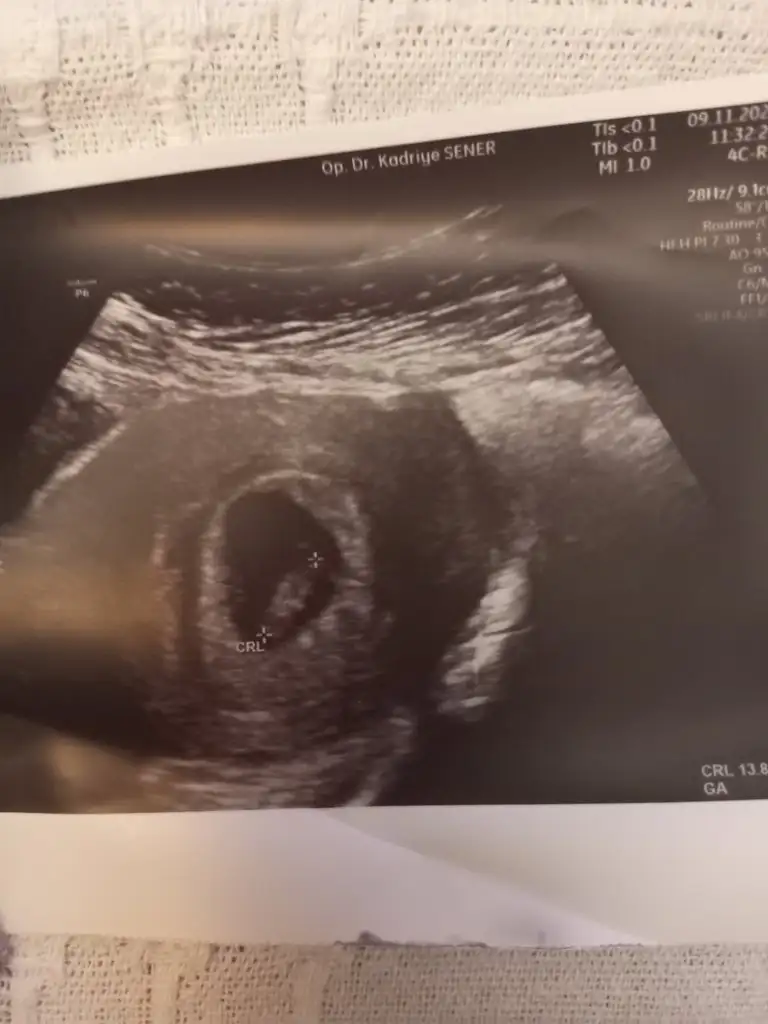

7+2 vajinal ultroson bende merak ettim 😂🤍

• IMG-20221130-WA0002.webp

IMG-20221130-WA0002.webp

22,8 KB · Görüntüleme: 115